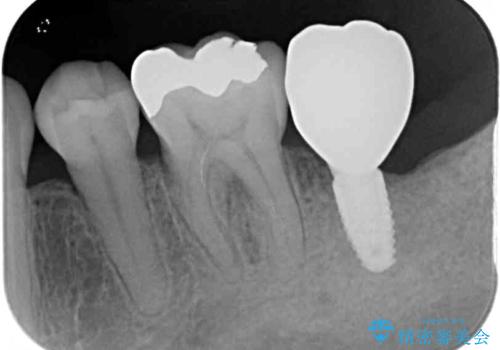

治療期間を短縮できるだけでなく、世界中で高い信頼を得ているストローマンインプラントを用いて治療を行うこととしました。

治療期間を短縮することが可能となった、ストローマン社のSLActiveというインプラントを使用し、抜歯からクラウンが装着されるまで6ヶ月という短期間で終えることができました。

咬み心地はもちろん、清掃性もご自分の歯とほとんど変わらない状態となり、患者様には大変満足していただきました。